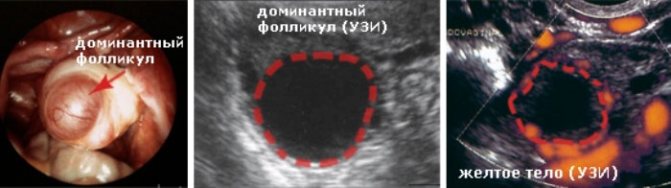

Желтое тело находиться в матке, а не как думают некоторые девушки и женщины, в маточных трубах или где-либо еще вне яичников. Оно всегда строго развивается исключительно на яичнике, где произошла овуляция. Яичников у женщины два. Фолликулы растут на обоих в самом начале нового цикла, но доминирующий обычно один, остальные проходят обратное развитие. Расположен доминантный фолликул либо на правом, либо на левом яичнике.

Желтое тело просматривается в области яичников и выглядит как небольшой мешочек, анэхогенное образование. Эхогенность отсутствует, поскольку внутри временной железы имеется определенное количество жидкой среды. Железа образуется сразу после овуляции, но разглядеть ее на УЗИ можно только через 3-4 дня после нее, поскольку размеры желтого тела на начальной стадии формирования очень незначительны.

Доктор замеряет диаметр при наличии временной железы в правом или левом яичнике. Показатель диаметра показывает насколько соответствует желтое тело стадии своего развития. Для оценки работоспособности железы измеряют толщину эндометрия.

1. 10 ый день цикла. Первая процедура проводится за 3-4 дня до предполагаемого разрыва фолликула. В этот период уже видно доминантный фолликул.

2. 12-13 день. УЗИ отображает наличие доминантного образования в яичнике.

3. 15-16 день. Наступление овуляторной фазы. Фаза длится всего день, после нее яйцеклетку уже не оплодотворить.

4. 18-19 день. Подтверждение произошедшего выхода яйцеклетки в полость матки. На мониторе отчётливо будет видно образование с размытыми контурами — желтое тело.

Женщине следует делать УЗИ на овуляцию каждые 2-3 дня. За этот промежуток времени фолликулы увеличиваются на 5-6 мм. Параллельно ведется наблюдение за увеличением толщины эндометрия. УЗИ на овуляцию позволяет обнаружить доминантный фолликул. Он отличается на фоне остальных своими объемами. Яйцеклетка становится зрелой тогда, когда размер фолликула достигает 18 мм. Это значит, что через 1-2 дня у женщины наступит овуляция.

В целях успешного зачатия в эти дни желательно практиковать половую близость. Эндометрий к моменту созревания ооцита должен достигать 10-13 мм. Момент овуляции на УЗИ выглядит неоднозначно. Доминантный фолликул пропадает, что может указывать на его разрыв. Но такой признак может свидетельствовать и о лютеинизации. Фолликул сдувается, но ооцит из него не выходит. В этом случае беременность становится невозможной. Определить, разорвался ли фолликул, поможет УЗИ после овуляции.

Признаки овуляции на УЗИ

На УЗИ после овуляции можно обнаружить признаки того, что фолликул лопнул. Их оценивают не отдельно друг от друга, а в совокупности. Овуляция на узи будет обнаружено в том придатке, где формировался доминантный фолликул. Оно необходимо для поддержания оптимального уровня прогестерона в организме в том случае, если произойдет зачатие. УЗИ на овуляцию позволяет не только определить его наличие, но и оценить качество кровотока. Уже на этом этапе врач может сказать, насколько высока вероятность зачать ребенка.

УЗИ после овуляции также покажет незначительное количество жидкости за маткой. Она рассасывается примерно через 2-3 дня после разрыва фолликулярных оболочек. Остальные фолликулы начнут регрессировать сразу после визуализации доминантного. После овуляции они полностью исчезнут.